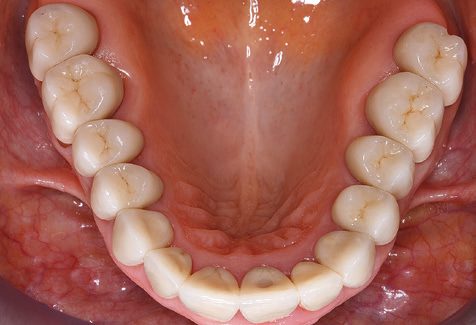

Abb. 9: Die Politur der zugänglichen Implantat­ und Zahnoberflächen erfolgt mit Polierkelchen und geeigneten Polierpasten. – Abb. 10: Die Reinstruktion zur Anwendung geeigneter Hilfsmittel bei der häuslichen Mundhygiene sollte ebenfalls Bestandteil der UPT sein. – Abb. 11a und b: Klinische Situation zwölf Jahre nach Insertion der prothetischen Versorgung. In diesem Zeitraum kam es lediglich zu einer Verblendkeramikfraktur am Zahn 47 und der Notwendigkeit einer endodontischen Behandlung am Zahn 12. Sämtliche Restaurationen sind noch in Funktion.

Für den klinischen Langzeiterfolg des parodontal kompromittierten Patienten ist die standardisierte und regelmäßige risikoadaptierte Betreuung im Rahmen der UPT der zentrale Baustein des Behandlungserfolgs. Dies gilt in besonderer Weise für Patienten, die nach erfolgreich abgeschlossener parodontaler Sanierung mit Implantaten versorgt wurden (Abb. 11a und b).